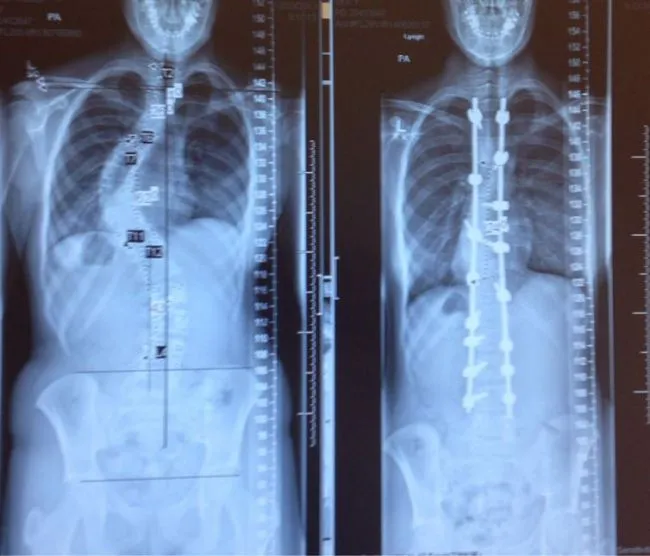

14 ภาพเอกซเรย์ที่เปรียบเทียบระหว่างก่อนและหลัง การรักษากระดูกสันหลังคด